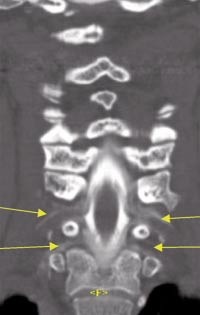

Etter 15 dager med strengt sengeleie og epidural blodlapp lagt i torakalt nivå var hun bedre og kunne utskrives, men ved poliklinisk kontroll etter to måneder angav hun fortsatt postural hodepine. Åpningstrykket ved spinalpunksjon var da 2 cm H₂O og lekkasjepunktene kunne identifiseres ved hjelp av CT-myelografi (fig 3). Behandling med tre blodlapper i cervikalt nivå og samtidig strengt sengeleie i ti dager gav symptomfrihet.

Radioisotopcisternografi viser typisk manglende aktivitet over de cerebrale konveksiteter og tidlig aktivitet i urinveier, og kan av og til også avdekke lekkasjenivå (5, 6). Det hevdes at lekkasjepunktet nesten uten unntak sitter spinalt og oftest i cervikotorakalovergangen eller torakalt (5). I praksis kan det være vanskelig å identifisere et eksakt lekkasjepunkt. CT-myelografi har vist seg å ha størst sensitivitet (4, 12, 13), men det anbefales at man grovsorterer med ikke-invasive undersøkelser som spinal MR, isotopcisternografi eller MR-myelografi før man gjør multiple CT-skanninger på antatt sannsynlig nivå (12).

Cerebral MR med gadoliniumkontrast ble gjort hos fire av våre pasienter, og kunne bekrefte diagnosen hos alle disse. Hos en pasient ble det gjort isotopcisternografi. Funnene var typiske for spontan intrakranial hypotensjon, men lekkasjenivå kunne ikke angis. Hos en annen pasient viste spinal MR epidural væskeansamling i øvre cervikalcolumna, men ikke noe sikkert lekkasjepunkt. CT-myelografi påviste lekkasjepunktene hos denne pasienten.